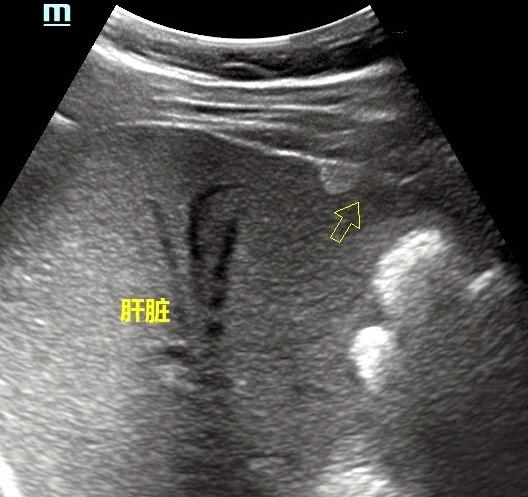

腹部超声主要对肝胆胰脾肾这几个器官进行观察,观察它们的形态大小,观察它们是否有其它占位。

肝脏较常见的良性占位有肝囊肿、肝内血管瘤。

恶性肿瘤(肝癌)也是能够发现的。